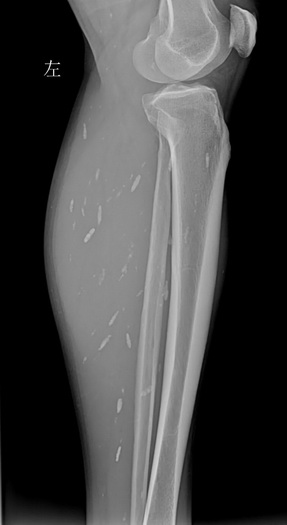

X光片显示,左小腿和右小腿分布着零散的囊虫,头部MR进一步显示,小脑半球内已聚集形成了一个较大的囊性占位……看着这些触目惊心的图片,刘宇(化名)觉得头脑发麻,没想到自己身上有这么多囊虫在潜伏。

(左小腿X光片,见肌肉内多发囊虫病灶。)

令人吃惊的是,除了头部,影像检查还提示,患者双下肢也有囊虫,分散密布在左小腿和右小腿处。吴杰表示,囊虫病是猪肉绦虫的幼虫寄生在人体各组织如脑、眼睛、皮下组织及肌肉等引起的疾病。如果囊肿进入大脑,可导致颅内压增高、癫痫或精神障碍等。该患者前期的癫痫发作及后期出现的头痛症状,都是脑囊虫病引起颅内占位性病变所致。